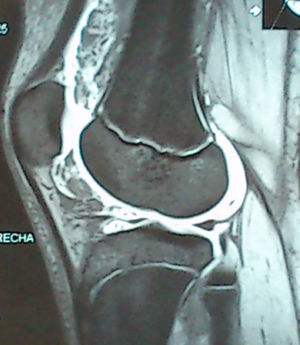

Right knee NMR: there was a small Baker's cyst on the medial side of the popliteal fossa and a moderate joint effusion in the suprapatellar recess. In the middle of the effusion there was a marked thickening of the synovial membrane that gave it finger-like or polypoid images, and occupied the suprapatellar recess, Hoffa's fat pad and the part adjacent to the cruciate ligaments and menisci. These formations had a signal like that corresponding to fat. After the intravenous administration of the contrast medium, there was an enhancement marked by the synovium that surrounded the polypoid lesions. This image was the confirmation of lipoma arborescens (Fig. 1).